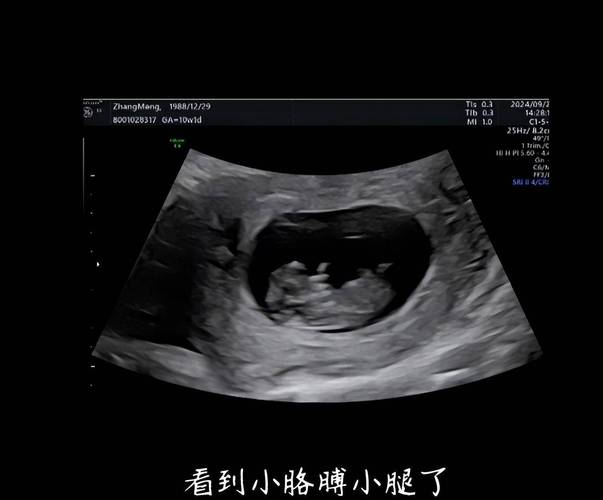

CRL ( Crown-rump Length ) - 头臀长

- 含义:测量胎儿从头顶到臀部(坐骨结节)的距离。

- 作用:在孕早期(11-13周+6天),这是推算孕周最准确的方法,也是NT检查的基础。